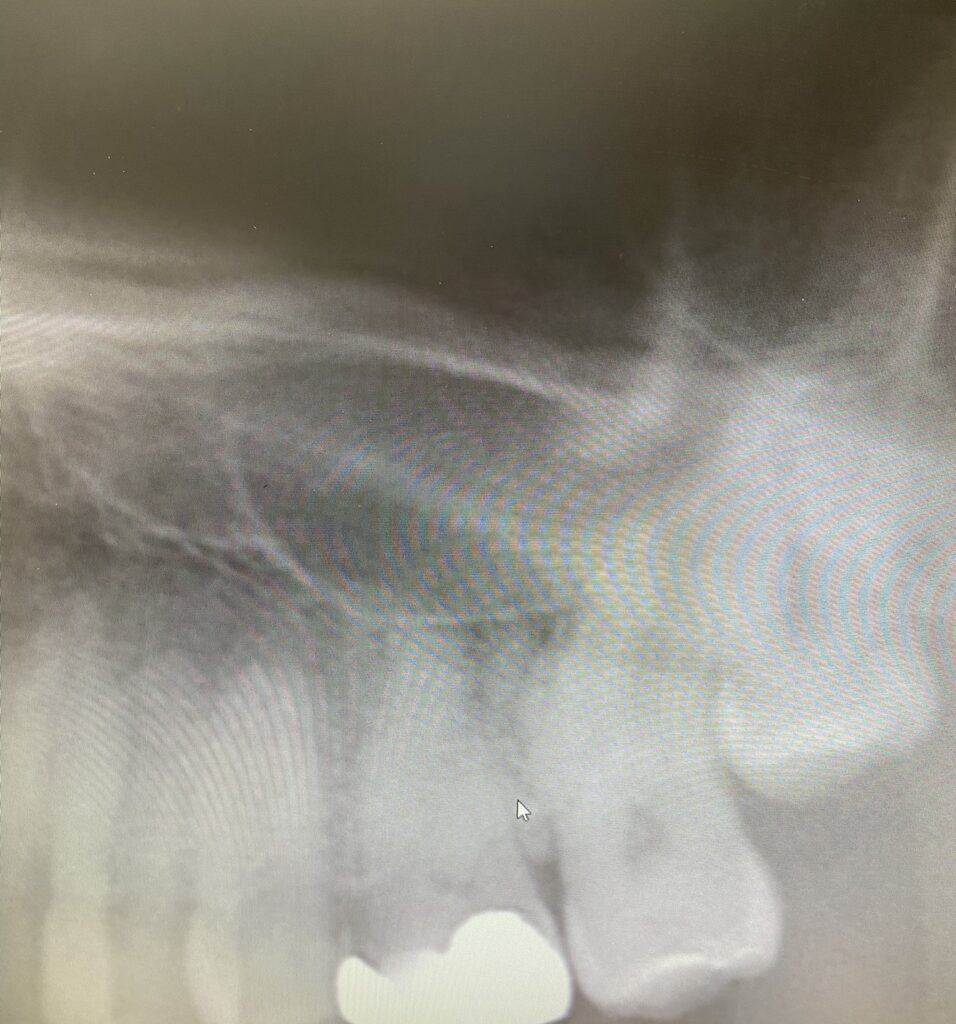

上の奥歯(特に第一大臼歯や第二大臼歯)の根っこは、この上顎洞のすぐ下に位置しています。人によっては、歯の根の先と上顎洞の底がとても近く、まるで隣り合わせのような構造をしています。

そのため、上顎洞に炎症が起きると、奥歯の周りに「響くような痛み」や「噛むと重い痛み」を感じることがあるのです。

歯に大きな虫歯や根尖病巣(歯の根の先にできる膿の袋)があると、その感染が上顎洞に波及して炎症を引き起こすことがあります。